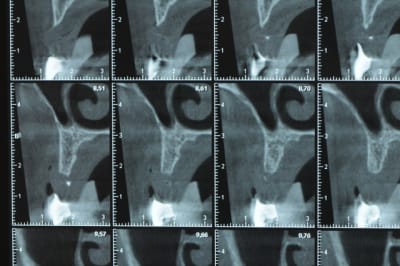

Une petite étude de ton cas D57

Sous réserves bien sur de voir l’animal en vrai

Les zones exploitables radiologiquement parlant:

Coupes implant

2,3 40100

4,96 35130 avec sinus lift mais difficile

5,25 35150

6,02 35130

6,78 35115 après réduction de hauteur de crête

7,26 35115 après réduction de hauteur de crête

8,51 35150

10,43 40115 ou 50115

11,10 40115

Ce qui nous fait 9 implants possible évidement avec un comblement de sinus on augmenterait encore les zones implantable mais ce n’est pas le but recherché, avec 8 (4+4) il doit être possible de faire une belle barre support de complet